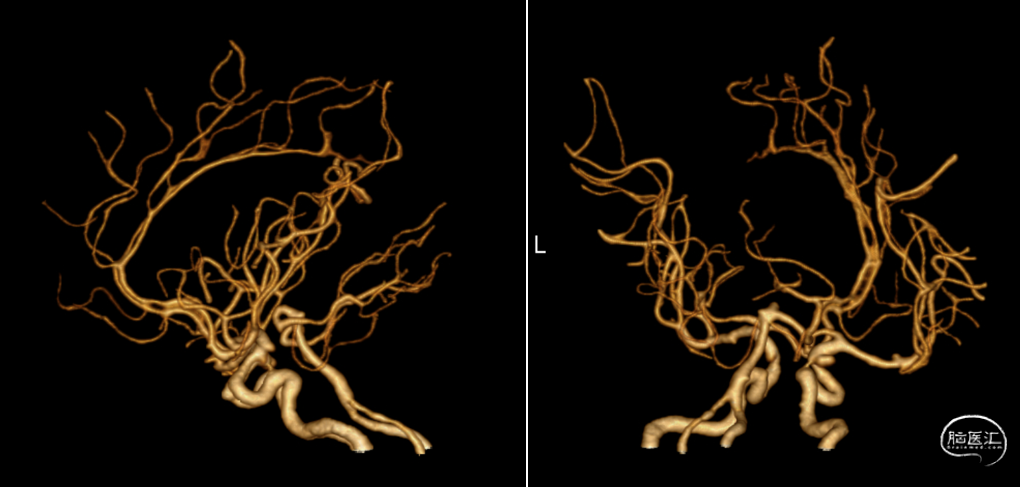

我院CTA

DSA

左侧多发动脉瘤